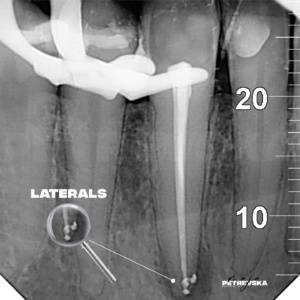

Најчесто забот е веќе „умртвен“, па оваа процедура е безболна и нема потреба од анестезија. Но, кога при некои дијагнози делови од нервот се сепак осетливи, процедурата се изведува со локална анестезија и е безболна. Каналите на коренот на забот треба механички и хемиски да се исчистат и дезинфицираат, а потоа прецизно (до дел од милиметар), да се наполнат со трајно ендодонтско полнење.

Во  ВЕГА, за ендодонтски третман на забите користиме неколку современи системи за работа, кои вклучуваат апаратура специјализирана за таа намена . Со неа, со извонредна прецизност (во дел од милиметарот) ја мериме должината на коренските канали. Истите ги дезинфицираме и овозможуваме успешно лекување и непречено функционирање на „умртвените“ заби. При третманот за постигнување на највисока можна прецизност користиме и дигитален рентген, како и специјални лупи за што попрецизно работење. За сушење на работното поле користиме систем на кофердам.